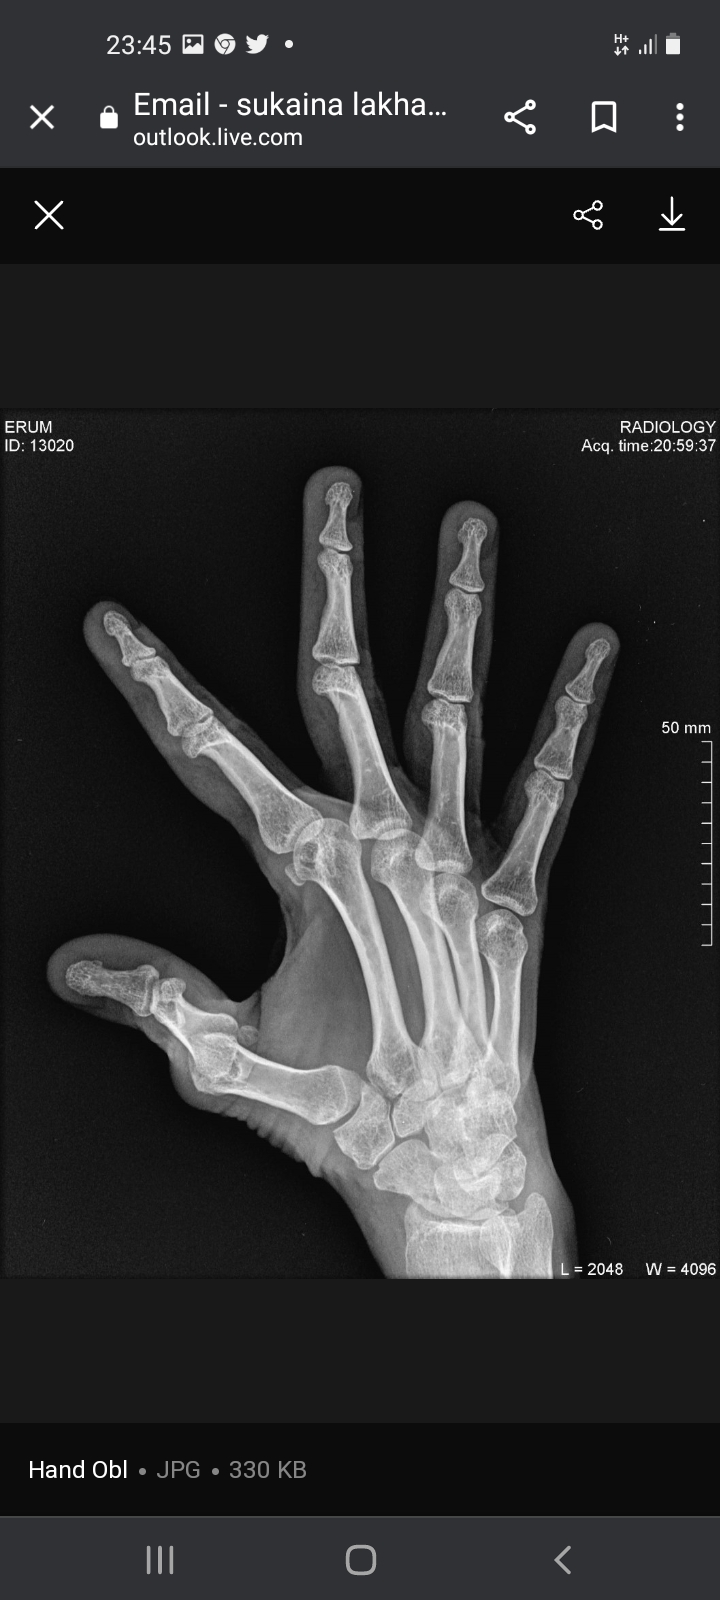

Not sure which treatment you are referring to. the Xrays show quite a bit of damage for someone who is just 40 yrs old. I suspect the patient may have inflammatory arthritis causing this. for this she should consult a qualified Rheumatologist for specialist treatment

I agree with Dr. Ashar, you are too young to have these x rays. See a rheumatologist soon.